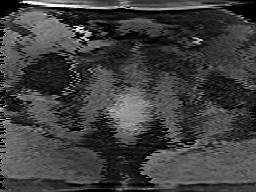

Tables 1 and 2 show our quantitative results: PSNR between the style (image we want to transfer style from) and generated image, SSIM and MS-SSIM between the content (image we want to take structure from) and generated image and finally, our proposed weighted SSIMs. For each style transfer direction and metric, our method consistently outperforms the other approaches. Figures 2 and 3 qualitatively highlight the good results of our method on 2D and 3D datasets. In addition, quantitative results on both figures show that our proposed metric preserves qualitative ordering of results for both style and content. In comparison, metrics such as SSIM struggle to accurately correlate to visual results.

Qualitative evaluation shows that the proposed method leads to sharper images, better content preservation, better localised CE and realistic MRI appearance. Quantitatively, we outperform the other algorithms with each metric, for each style transfer direction. While we expected that adding CE to images would be an easier task than removing CE, we found that for both tasks the method exhibits similarly performing quantitative and qualitative results. The results for style transfer with the kidney data show that when there is clear CE, it is easier to perform style transfer in both directions. However, when style transfer is performed on the prostate data, the model struggles in comparison to the kidney data. This may be due to the enhancement of the prostate being less defined than the kidney data. In figure 3(b), we can see the prostate with CE. Compared to figure 2(b) showing kidneys with CE, it is harder to determine the edges. The two original images shown in figures 3(a) and 3(b) are clear and easy to see some edges of prostate, in other images, it is harder to see the edges of the prostate.

(C) CW-SSIM: 0.93

(S) CW-SSIM: 0.62